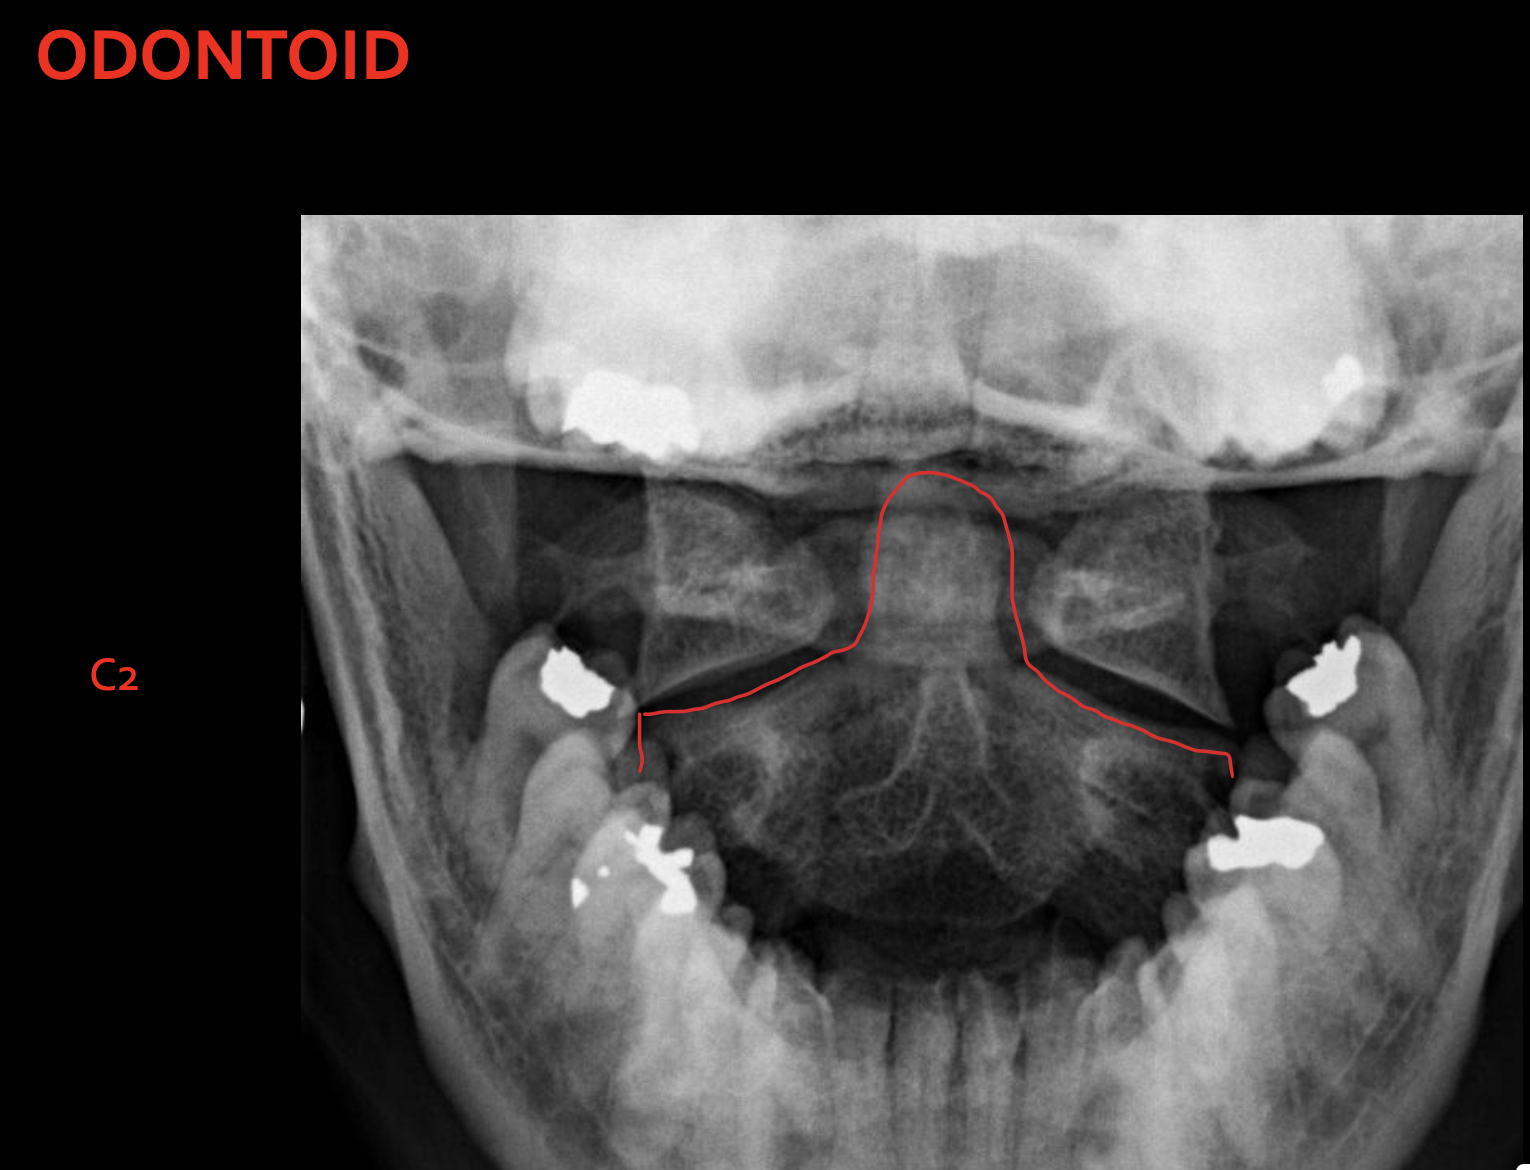

齿状突(枢椎齿突)

Odontoid

C2